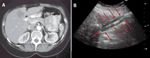

FIGURE 1

Percutaneous Cryoablation

Another disadvantage of percutaneous approaches to liver tumors is the lack of a thorough evaluation of the abdominal contents to assess for extrahepatic disease and the lack of intraoperative ultrasound, which detects additional sites of hepatic disease in 40% to 55% of patients.[4-6] Although percutaneous ablation has historically been limited in its ability to safely treat lesions near other structures, the use of ablation with displacement techniques such as infusions of saline or dextrose in water or air, or physical barriers such as balloons, has made it possible to perform an increasing number of these procedures safely (Figure 1).